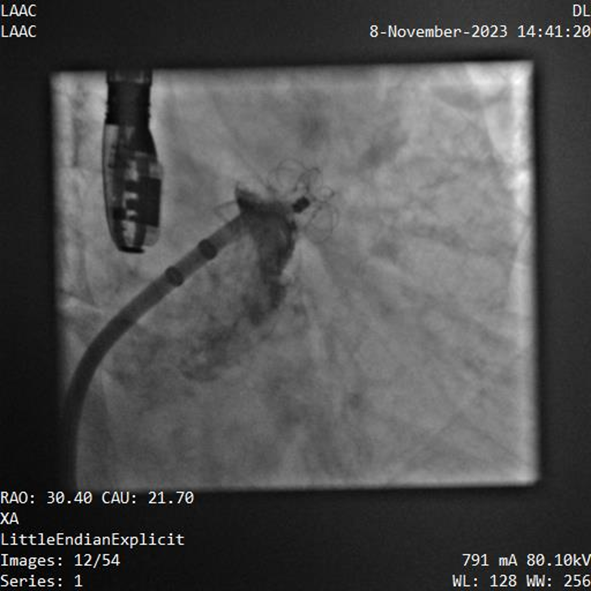

該例患者為男性58歲,陣發(fā)性房顫,9個月前突發(fā)急性腦梗死,3月前曾行房顫射頻消融術。2023年11月經胸超聲心動圖示左房內徑46mm,經食道超聲心動圖示左心房及左心耳內未見血栓形成,CHA2DS2-VASc評分3分,HAS-BLED評分2分。DSA測得左心耳開口直徑約23mm,錨定區(qū)域約18mm。

葛均波院士、周達新教授等經詳細評估和討論后,認為該受試者需要植入固定部20mm、封堵盤28mm的左心耳封堵器,為非常規(guī)固配規(guī)格,SimuLock的可選配組裝式設計精準滿足患者需求。

手術過程順利,通過植入非常規(guī)固配規(guī)格的固定部20mm、封堵盤28mm的左心耳封堵器,實現左心耳完全封堵,達到手術預期效果,再次體現產品獨特的設計創(chuàng)新優(yōu)勢。

器械釋放后造影示封堵器展開良好,封堵完全